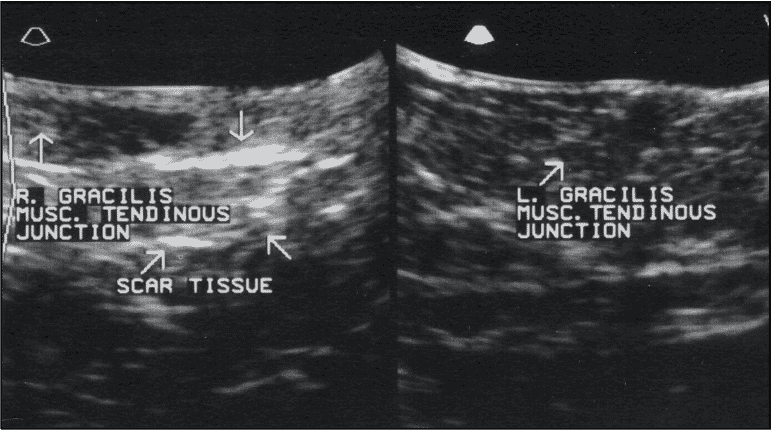

La tomodensitométrie (TDM) fournit beaucoup plus d'informations que les radiographies simples, en particulier dans les cas chroniques où des zones de minéralisation dystrophique peuvent s'être formées. La tomodensitométrie est inestimable dans les cas de traumatismes aigus qui peuvent avoir subi des lésions d'avulsion subtiles. L'échographie est devenue la modalité initiale de choix pour l'évaluation d'une variété de lésions musculo-tendineuses. En termes généraux, les régions hypoéchogènes représentent des lésions récentes et montrent des régions d'hémorragie et/ou de liquide, tandis que les régions hyperéchogènes représentent des régions de fibrose et de tissu cicatriciel plus typiques d'une lésion chronique Figure 3). L'échographie peut également fournir des informations supplémentaires en temps réel pendant que le tissu concerné est soumis à différentes amplitudes de mouvement.